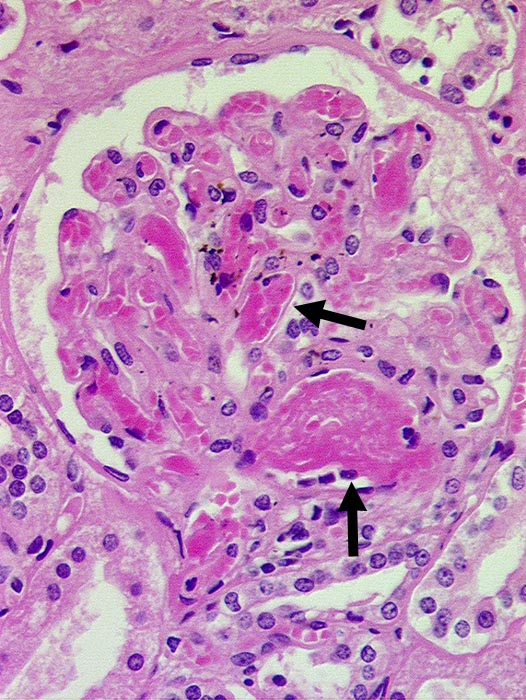

PathoPic ID 109 - Nierenglomeruli mit DIC

Nierenglomeruli mit DIC

vaskulär / Durchblutungsstörung

Niere

Die glomerulären Gefässe sind angefüllt mit azellulären Fibrinthromben.

Paraneoplastische DIC bei metastasierendem Mammakarzinom

Histologie